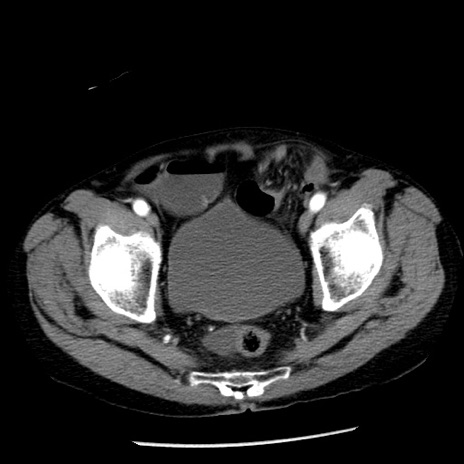

症例26(横断像)

【症例】80歳代男性

【主訴】嘔吐

【現病歴】昨晩2回嘔吐あり、今朝になっても嘔吐あり。来院。

【既往歴】胃潰瘍

【身体所見】意識清明、BT 37.6℃、BP 166/95mmHg、HR 100bpm、SpO2 97%、腹部:平坦・軟、腸蠕動音聴取良好、圧痛なし。

【データ】WBC 21900、CRP 1.46